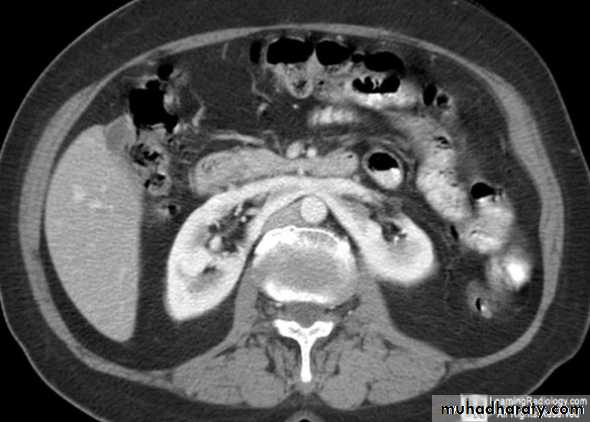

CT scanContrast enhanced CT scan through the kidneys in nephrogram phase 90-100 seconds following contrast administration and would show renal lesions well.

Contrast enhanced CT scan through the kidneys in pyelogram phase (showing excretion of contrast into the collecting system). This is approximately 10-15 minutes following contrast administration and would show urothelial lesions well, such as transitional cell carcinoma, stones, blood clots.

Cortico-medullary phase: After 35-40 seconds:

The only parts of the renal tract which have enhanced are the renal arteries and the cortex.Useful for evaluation of the renal arteries (which may be reformatted as CT angiogram) and for evaluation of highly vascular renal tumors.

Native CT…For evaluation of any renal stones or abnormal calcification.